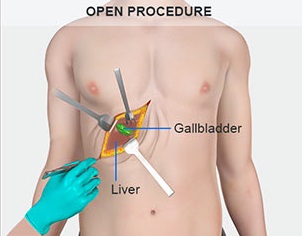

Overview

Package includes:

Days in hospital : 2 to 3 Days (For patient and one attendant)

Days in hotel : 7 Days (For patient and one attendant)

Room type in hospital : Shared

Room type in hotel : Private

Hotel category: Standard

Value added benefits of the Open - Cholecystectomy:

Ø Doctor consultation charges

Ø Lab tests and diagnostic charges

Ø Room charges inside hospital during the procedure

Ø Surgeon Fee

Ø Nursing charges

Ø Hospital surgery suite charges

Ø Anesthesia charges

Ø Routine medicines and routine consumables (bandages, dressings etc.)

Ø Food and Beverages inside hospital stay for patient and one attendant.

Extra benefits:

ü Interpreter

ü Visa assistance

Ø Site tourism of the city

Ø Follow up with the doctor

Ø Airport pick up and drop

Ø Free online consultation with the doctor

Ø Priority appointments with the doctor

Ø Room upgrade from sharing to private